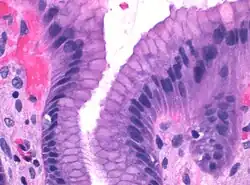

Microscopic section of gastric mucosa. Foveolar cells can be seen at top of the image lining the surface and pits

Foveolar cells or surface mucous cells are mucus-producing cells which cover the inside of the stomach, protecting it from the corrosive nature of gastric acid.[1][a] These cells line the gastric mucosa and the gastric pits. Mucous neck cells are found in the necks of the gastric glands. The mucus-secreting cells of the stomach can be distinguished histologically from the intestinal goblet cells, another type of mucus-secreting cell.

Foveolar cells line the surface of the stomach and the gastric pits. They constitute a simple columnar epithelium, as they form a single layer of cells and are taller than their width. Other mucus-secreting cells are the mucous neck cells in the necks of the gastric glands.[2]: 257